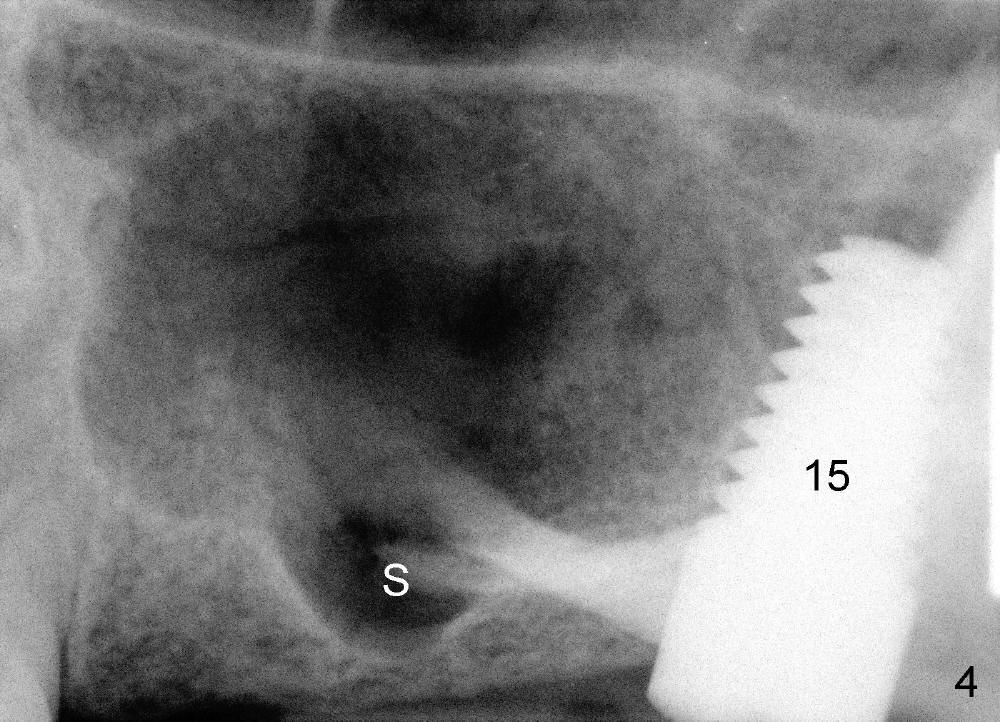

The two cases we discuss early appear to show that implants at the first molar are placed to engage in the mesial aspect of bone to have primary stability (1,2). But sometimes sinus floor may be right above the first molar (Fig.1-4). Fig.1 (CT sagittal) and 2 (coronal) were taken before #15 extraction, whereas Fig.3, 4 (PA) were taken during and immediately after extraction, respectively. A tapered 8x17 mm implant was placed at the site of #15.

In order to get primary stability, it is apparent that a large screw implant should be placed (Fig.1,2: 8x11 mm) to engage all of the lateral walls of the concave sinus floor (mesial and distal (Fig.1), buccal and lingual (Fig.2 B, L). Three millimeter shorter implant may be more appropriate (8x8 mm) in term of being less traumatic.